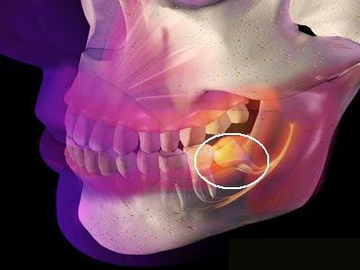

1、智齒位置:智齒的位置是影響拔除費(fèi)用的重要因素之一,智齒的位置越深,手術(shù)難度越大,拔除費(fèi)用也就越高。

2、手術(shù)復(fù)雜性:拔智齒手術(shù)的復(fù)雜性也會影響費(fèi)用,如果智齒生長位置正常,手術(shù)相對簡單;如果智齒被埋在骨頭里,需要切開牙齦和骨頭,手術(shù)難度增大,費(fèi)用相應(yīng)增加。